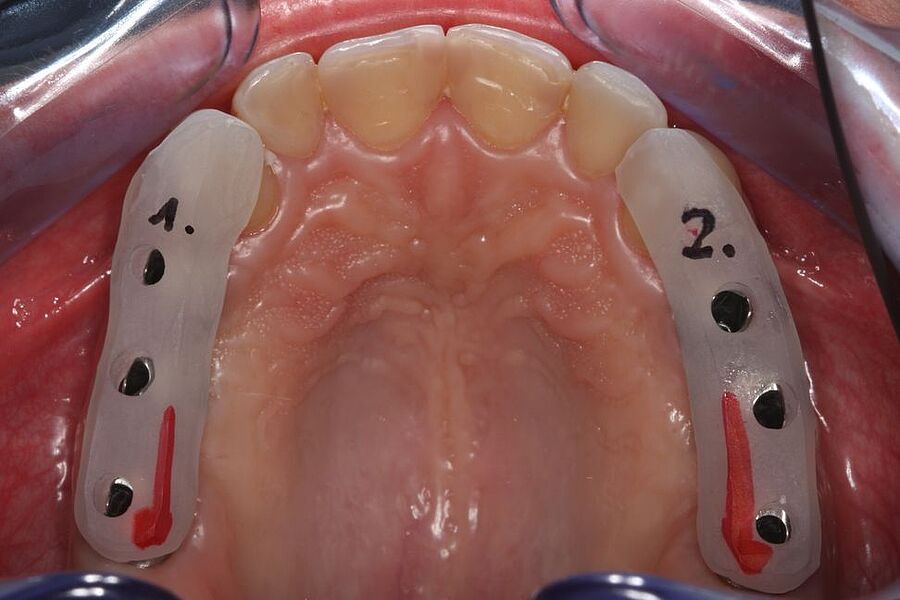

Im Journal Zahnmedizin up2date demonstrieren unsere Ästhetik-Spezialisten in einem weiteren Beitrag zum Thema professionelle Zahnaufhellung wie ein entsprechend angeleitetes At-Home-Bleaching funktioniert. Die entscheidende Vorbereitungsphase mit der Herstellung der Schienen und der adäquaten Instruktion des Patienten werden in dieser Publikation anhand eines Bildessays illustriert.

Zeitschrift: Zahnmedizin up2date

Ausgabe: 03/2023

Autoren: Dr. Helena Schmidt-Park,

Dr. Dr. Hans Ulrich Brauer, M.A., M.Sc.

In der Ausgabe 02/2023 der Fachzeitschrift Zahnmedizin up2date berichten unsere beiden Ästhetik-Spezialisten wie ein professionelles In-Office-Bleaching vitaler Zähne funktionieren kann. Die hierzu nötigen Arbeitsschritte einschließlich der klinischen Voraussetzungen werden Schritt für Schritt anhand eines Bildessays illustriert.

Ausgabe: 02/2023